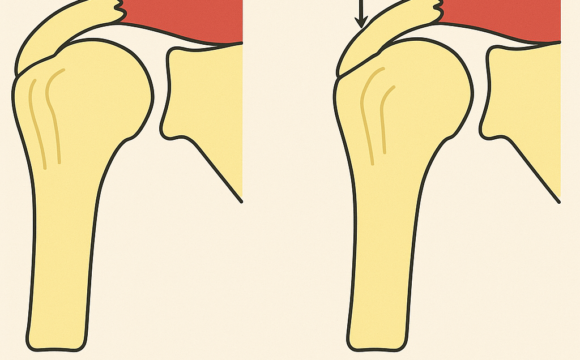

- Fracturi și luxații

- Deformări evidente ale oaselor sau articulațiilor

- Dureri de spate severe sau cronice